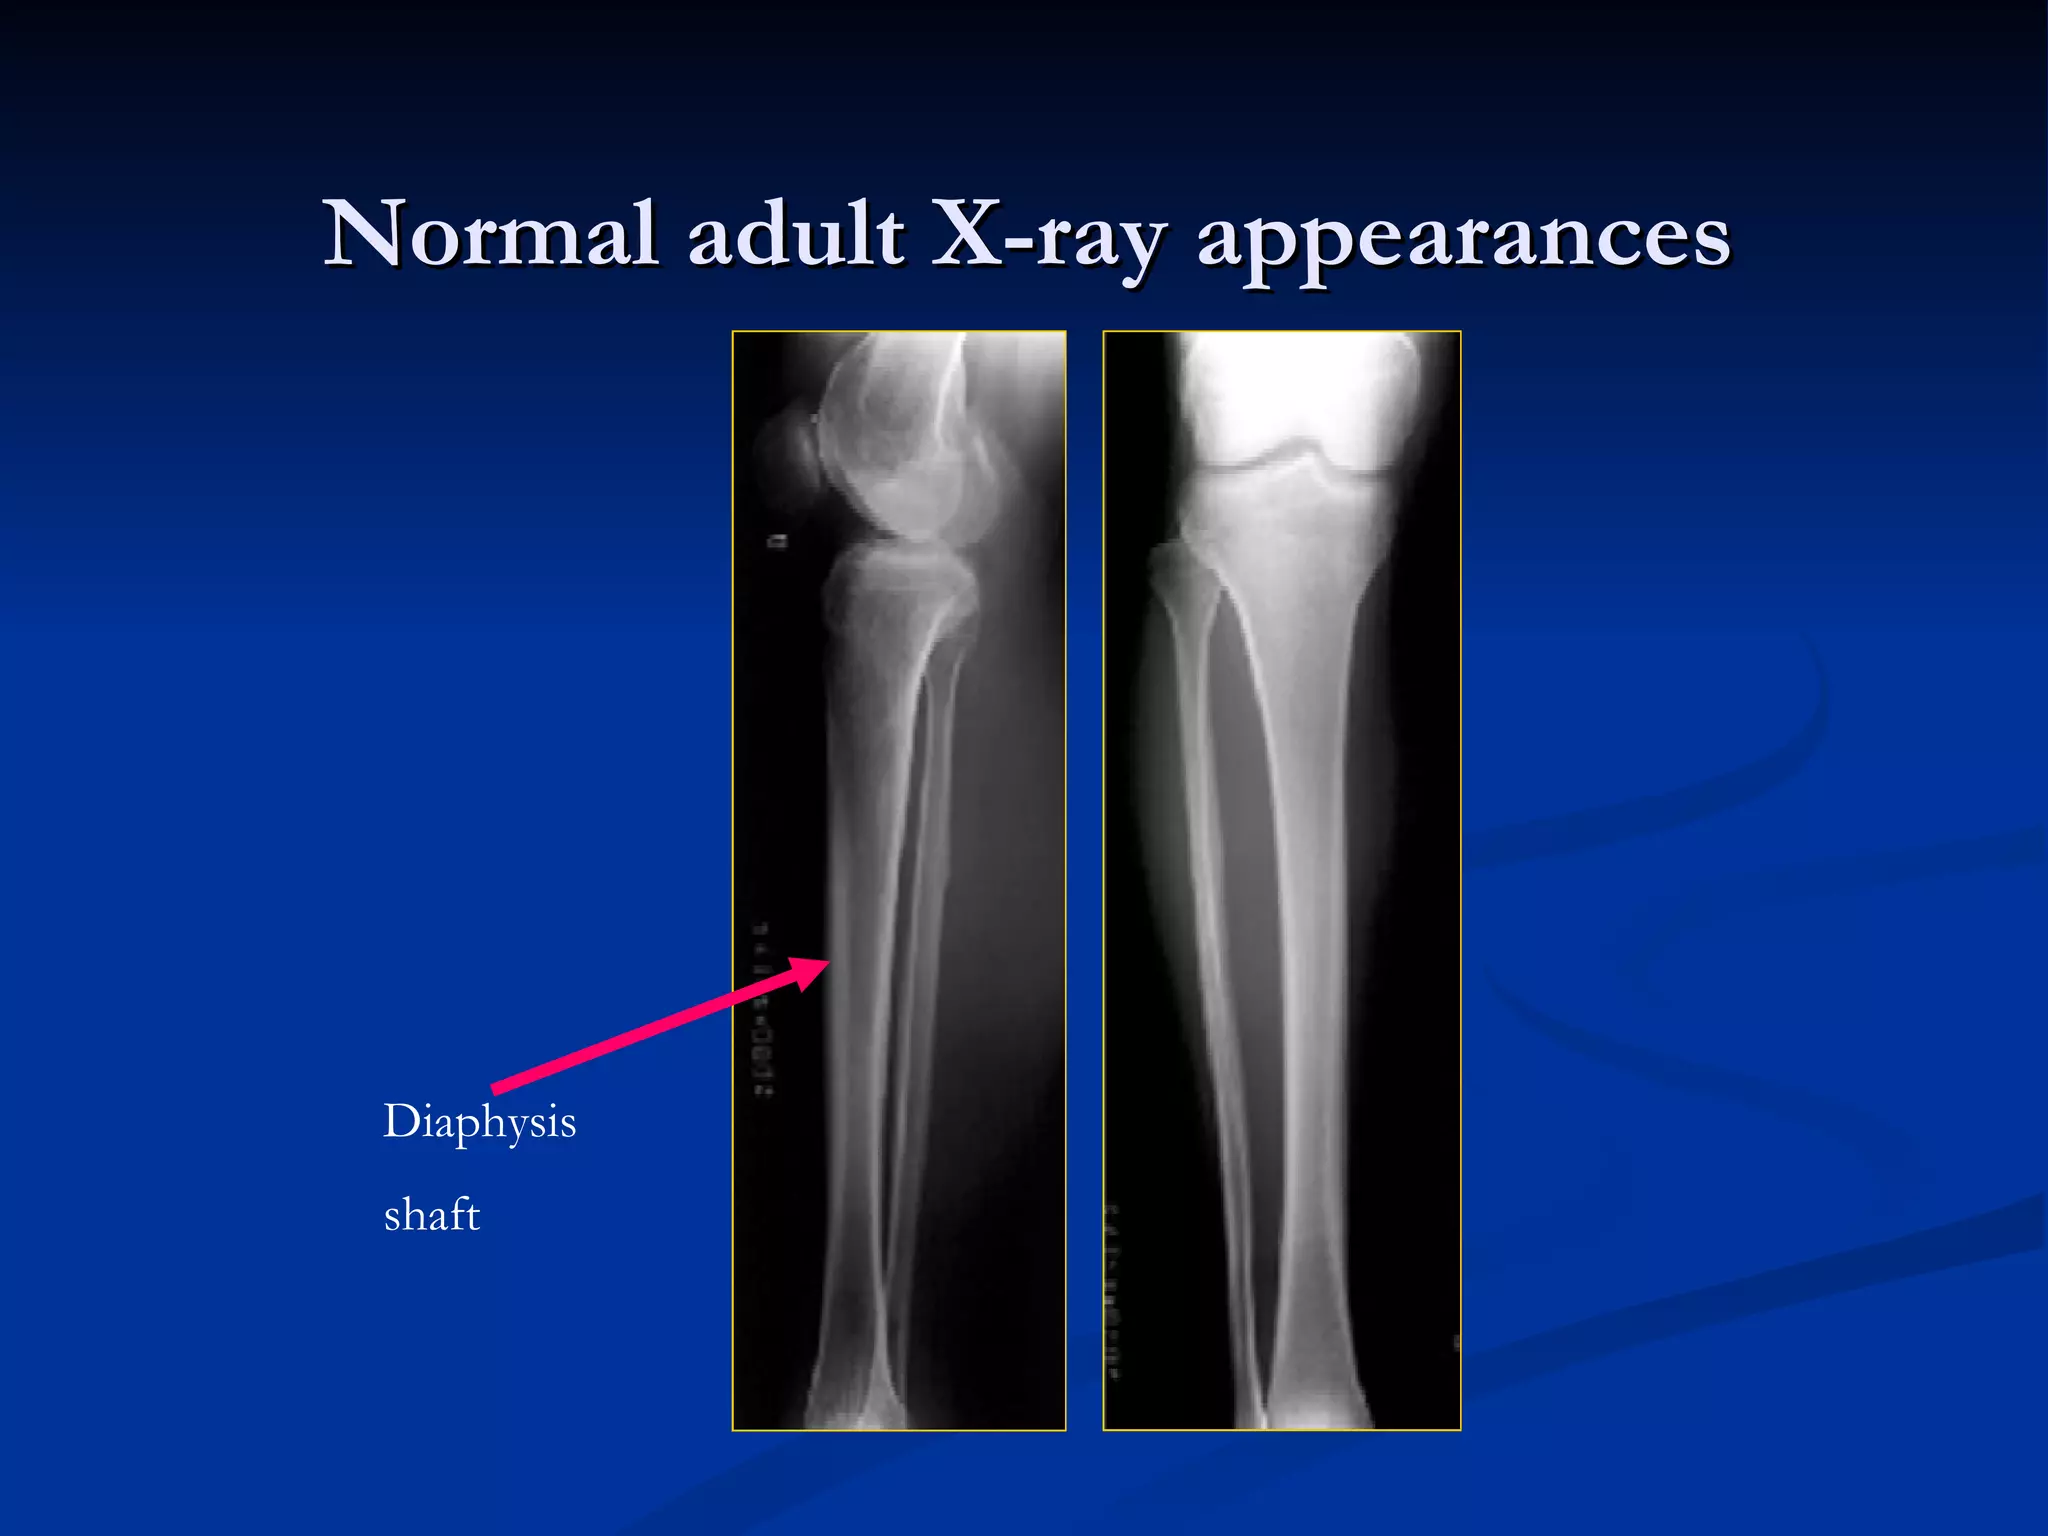

Normal adult X-ray appearances Diaphysis shaft

Normal X-ray appearances The types of skeleton: Long bone Pediatric  : diaphysis 、 metaphysis 、 epiphysis 、 epiphyseal plate Adult  : diaphysis (shaft) 、 Short bone Flat bone  –  hematopoiesis Irregular bone Joint

Normal adult X-rayappearances Diaphysis shaft

Normal X-ray appearancesThe types of skeleton: Long bone Pediatric : diaphysis 、 metaphysis 、 epiphysis 、 epiphyseal plate Adult : diaphysis (shaft) 、 Short bone Flat bone – hematopoiesis Irregular bone Joint